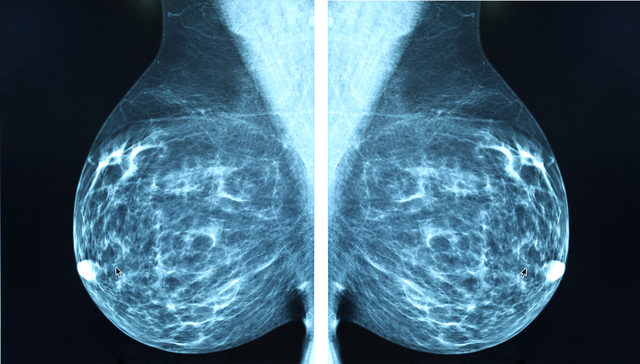

40 yaşından sonra mamografi: Elle muayenenin bir klinisyen tarafından yapılması ve yıllık mamografi çekimlerine başlanılması öneriliyor. 40 yaş üzeri kadınlarda herhangi bir şikayet olmasa bile 1 ya da 2 yılda bir yapılan mamografilerle meme kanseri erken saptanabiliyor. Mamografiyle elde edilen bilgiler yeterli gelmezse ek olarak ultrasonografi yöntemine başvuruluyor. Güçlü aile öyküsü olan ya da meme kanserine eğilim yapan genetik bozuklukları taşıyan kadınlarda daha erken yaşlarda ve farklı yöntemler kullanarak da tarama yapılabiliyor.